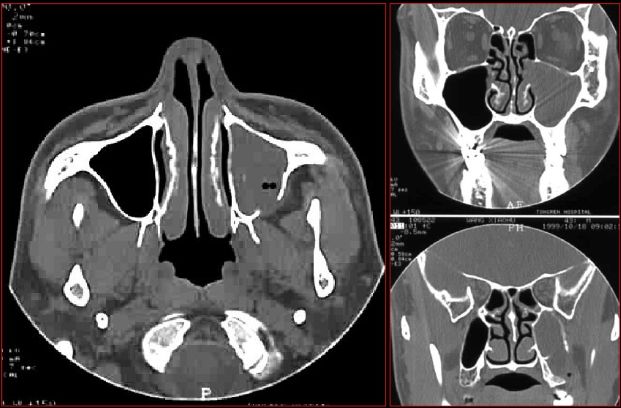

牙源性鼻窦炎